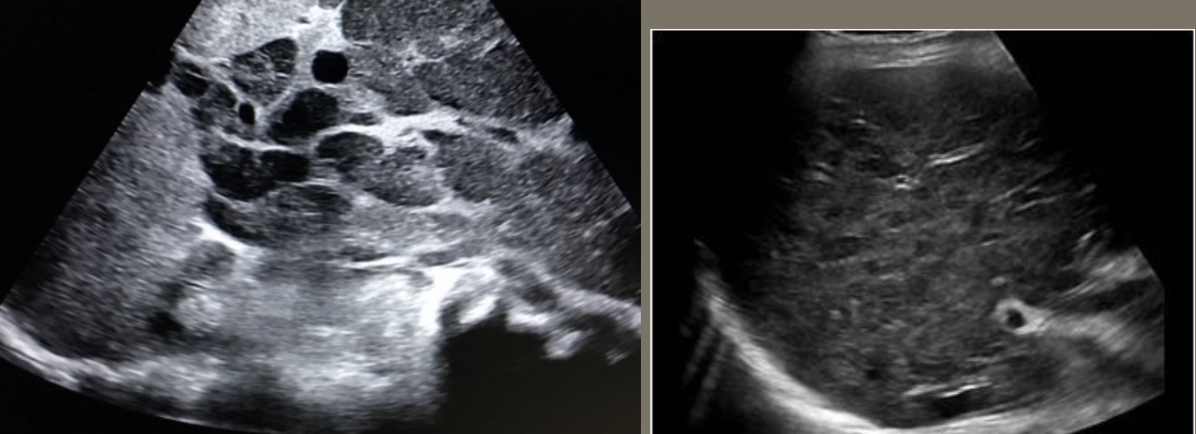

AAA (Abdominal Aortic Aneurysm) → focal dilation of aorta

2D US presentation: focally dilated AO (3 cm or greater), mural hypoechoic thrombus, wall calcifications, usually located infrarenal, can be fusiform or saccular

color doppler: turbulent helical flow

DDX: aortic dissection (aorta may be enlarged, but has intimal flap), pseudoaneurysm (focal outpouching w/ narrow neck, but not all 3 layers involved)